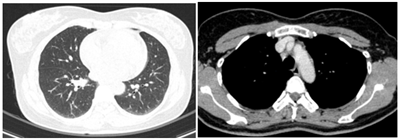

Case lâm sàng: Ứng dụng trí tuệ nhân tạo (Artificial intelligence – AI) trong chẩn đoán và điều trị sớm Ung thư phổi tại Trung tâm Y học hạt nhân và Ung bướu, Bệnh viện Bạch Mai

Case lâm sàng: Ứng dụng trí tuệ nhân tạo (Artificial intelligence – AI) trong chẩn đoán và điều trị sớm Ung thư phổi tại Trung tâm Y học hạt nhân và...

Theo GLOBOCAN 2022, ung thư phổi đứng đầu về số ca mới mắc (2.480.301 ca mới mắc chiểm 12.4%) và dẫn đầu số ca tử vong (1.817.172 ca tử vong chiếm 18.7%) trên toàn thế giới.  Tại Việt Nam tỷ lệ mắc...